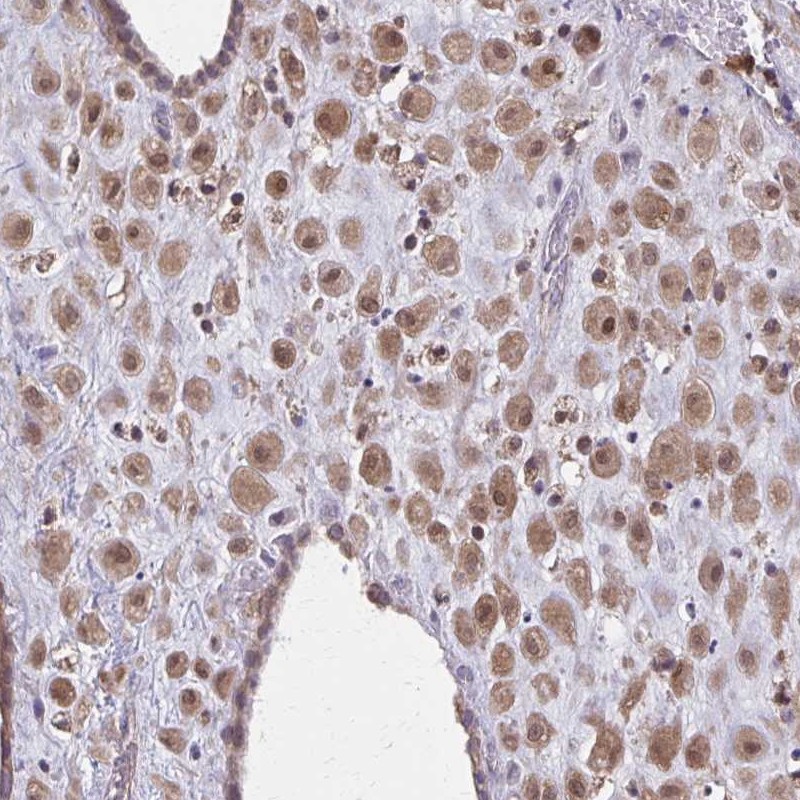

Immunohistochemical staining of human placenta shows moderate cytoplasmic and nuclear positivity in decidual cells.